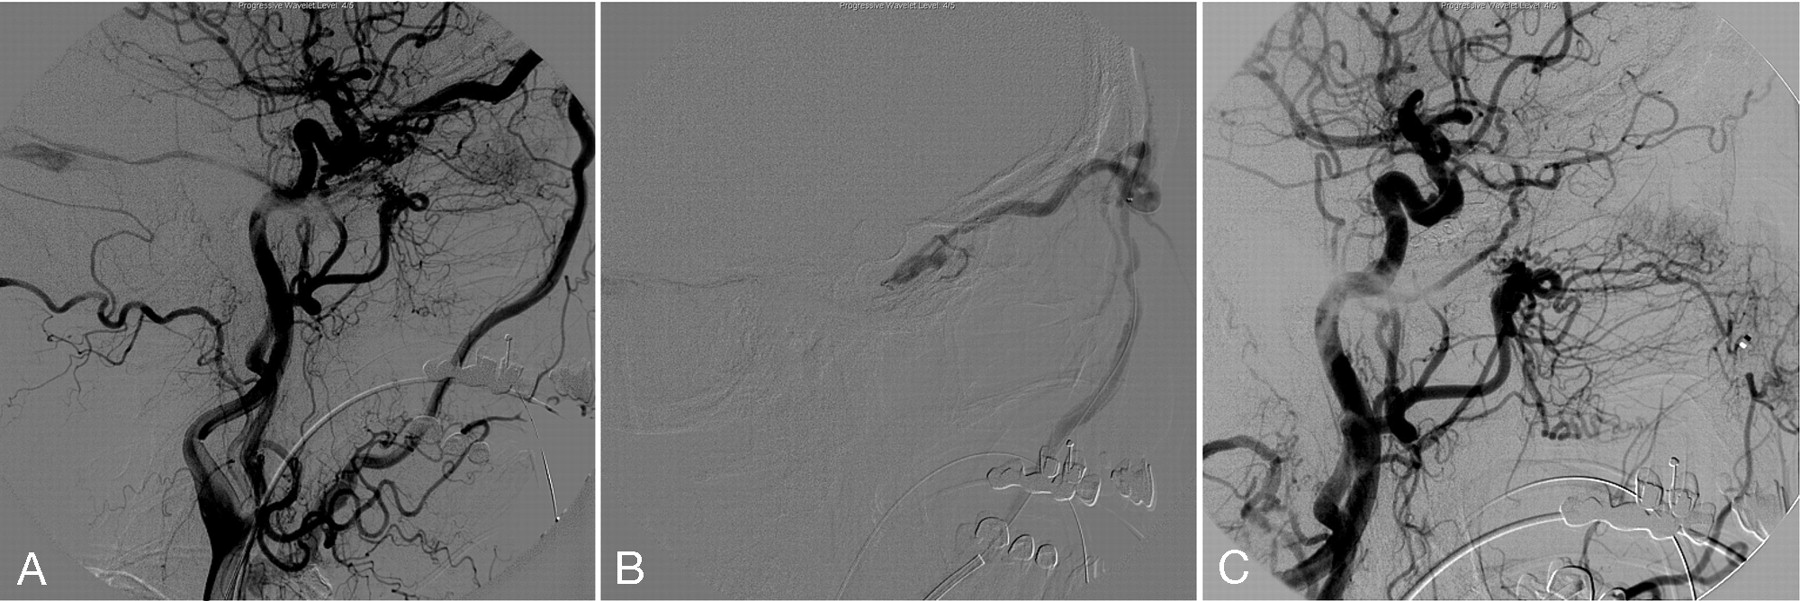

A 67-year-old woman, with well-controlled diabetes mellitus and hypertension, developed slowly progressing left eye injection, swelling, and blurry vision during a 3-week period. On the preprocedure physical examination, proptosis and significant conjunctival chemosis in the left eye were observed. The visual acuity was OS 20/200 and OD 20/70. Pupils were normal. Intraocular pressures were 8 mm Hg OD and 18 mm Hg OS. Left sixth and a partial third cranial nerve palsies were also identified. An MR image of the orbit disclosed an enlarged left superior ophthalmic vein (SOV). Right common carotid artery (CCA) injection showed an abnormal early venous drainage into the cavernous sinus. The main fistula site was located in posterior cavernous segment fed by dural branches of meningohypophyseal trunk. The left SOV was opacified in retrograde fashion through the coronary sinus. Early venous drainage was also seen in the posterior compartment of the cavernous sinus (left more than the right), extending into the inferior petrosal sinuses (IPS) and followed by cerebellar cortical veins (Fig 1A, -B). Through a femoral venous access, a 6F Envoy angled guiding catheter (Cordis, Miami Lakes, Fla) was positioned in the left internal jugular vein, at the orifice of the left IPS. Under road-mapping, an Echelon 14 microcatheter (Micro Therapeutics) and FasDasher 14 microguidewire (Boston Scientific Target, Fremont, Calif) were positioned in the left SOV through the left IPS. A total of 14 coils, using a combination of GDCs (Boston Scientific Target), Matrix II coils (Boston Scientific, Fremont, Calif) and HydroCoils (MicroVention, Aliso Viejo, Calif), were deployed into the proximal left SOV and the anterior aspect of the cavernous sinus (Fig 1C). However, multiple residual fistulas were identified on the control angiogram after coil deployment. The tip of the microcatheter was then placed among the deployed coils. Eight percent EVOH (Onyx 34) was prepared on a Vortex mixer (Scientific Industries, Bohemia, NY) for 20 minutes. The microcatheter was flushed with normal saline, followed by filling of the catheter dead space with dimethyl-sufloxide (DMSO). Onyx was slowly injected into the microcatheter dead space for 90 seconds and then embolization was started. The Onyx 34 was initially injected into the coil mesh and midsegment of the SOV (Fig 1D). The Onyx penetrated into the anterior compartment followed by posterior compartment of the cavernous sinus on the left side. Finally, the Onyx penetrated into the coronary sinus and entire dural fistula site (Fig 1E, -F). When we observed the reflux, we held the injection 30 seconds to 2 minutes to solidify the Onyx polymerization; the injection was then restarted (the reflux-hold-reinjection technique). A total volume of 2.5 mL was delivered for 46 minutes. Postprocedural neurologic examination showed marked improvement in visual acuity and ocular pressure. A partial left fourth cranial nerve palsy remained.

A, Pre-embolization right CCA. Frontal projection arterial phase shows the dural CCF with early venous drainage into the left cavernous sinus followed by the left IPS.

B, Lateral projection of right CCA injection late capillary phase shows retrograde filling of abnormally dilated left SOV.

C, Unsubtracted lateral projection image demonstrates transjugular-IPS venous access to the left SOV and deployed coils in the left SOV.

D, Lateral view of the right CCA injection shows the repositioned microcatheter to the anterior compartment of the cavernous sinus and partial embolization with Onyx.

E and F, Postembolization CCA angiogram. Frontal projection (E) and lateral projection (F) demonstrate complete obliteration of the fistula. Deployed coils in the left SOV and Onyx cast in the left cavernous and coronary sinuses block the fistula. There is no residual fistula.